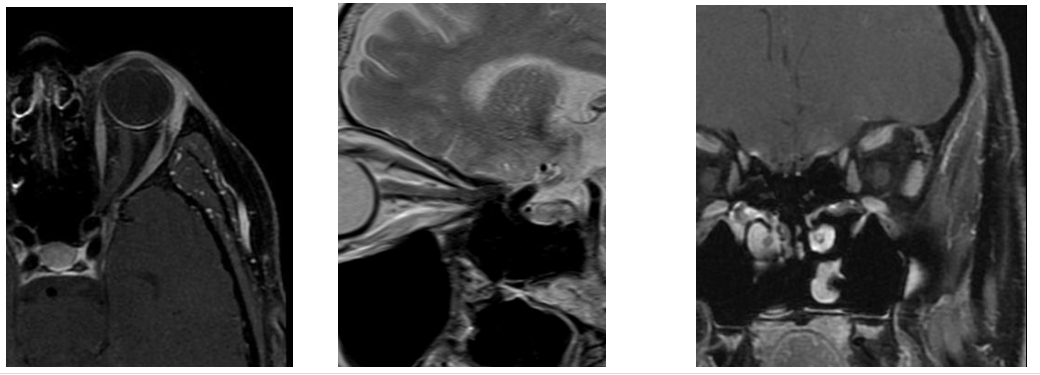

Chụp cộng hưởng từ hốc mắt và thần kinh thị giác có tiêm chất thuốc đối quang từ là kỹ thuật hiện đại, áp dụng rộng rãi trong chẩn đoán bệnh lý của nhãn cầu, bệnh lý của các cơ vận nhãn, các tổn thương trong nón (như bất thường mạch máu, viêm hoặc u dây thần kinh thị...); cũng như các tổn thương ngoài nón (như áp xe, u dây V và tổn thương xương...). Nó có độ phân giải cao để phân biệt các cấu trúc bệnh lý với các cấu trúc bình thường như nhãn cầu, dây thị, các cơ vận nhãn...

- Khi chụp cộng hưởng từ hốc mắt bệnh nhân sẽ được chụp hai thì. Thì ban đầu là chụp cộng hưởng từ sọ não thông thường và chụp khu trú vùng hốc mắt, thì thứ hai là chụp khu trú vùng hốc mắt tiêm thuốc đối quang từ. Thuốc đối quang từ thường dùng là Dotarem, giúp dễ dàng phân biệt sự khác biệt giữa mô bình thường và khối u, nhiễm trùng hoặc các bất thường khác.